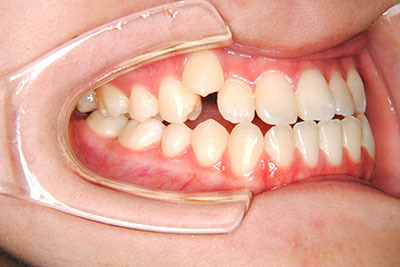

小学生高学年や中高生で矯正治療を考えている方へ

歯が乳歯から永久歯に生え変わった小学生高学年や、中高生でも矯正治療に手遅れということは全くありません。

成長中の顎の骨を矯正できたり、この時期の矯正はおとなになってから矯正治療を始めるよりも短期間で済むことがほとんどです。当院だとおおよそ1年で動的治療(マルチブラケット装置をつける期間)が終わることが多いです。